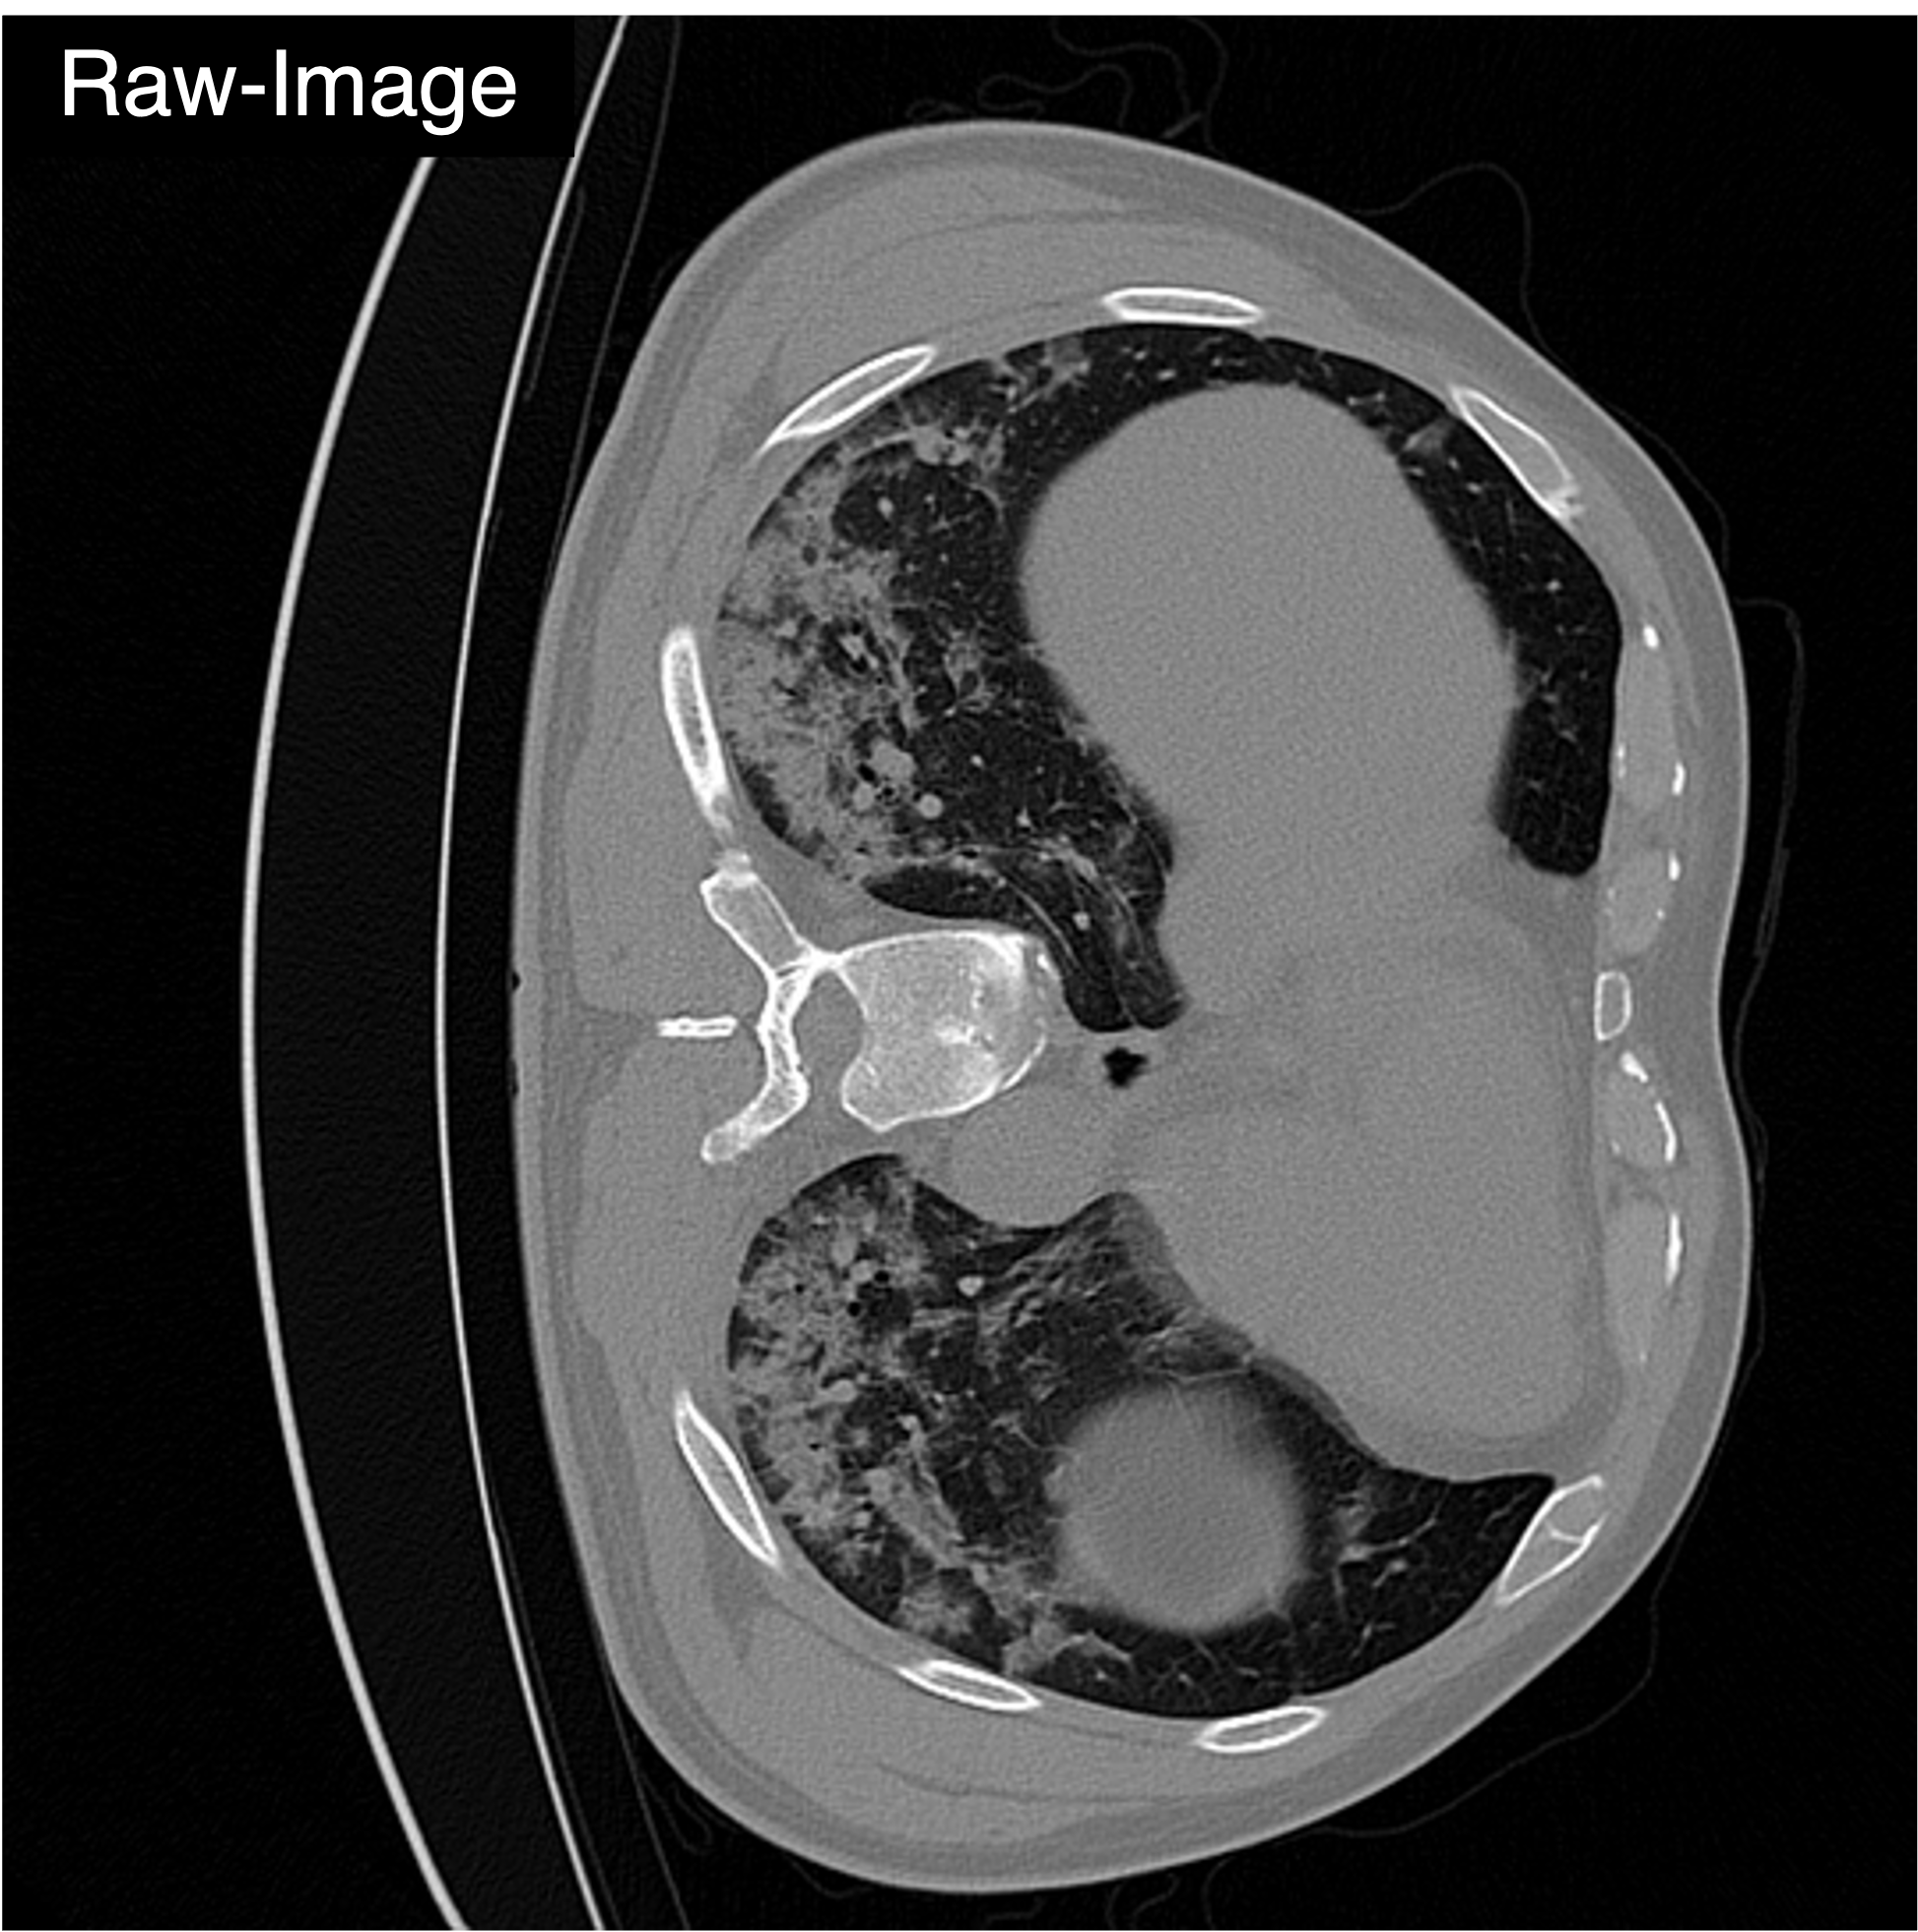

"COVID-19 infection in lung CT"

Medical object detection suffers when a single detector is trained on mixed medical modalities (e.g., CXR, CT, MRI) due to heterogeneous statistics and disjoint representation spaces. To address this challenge, we turn to representation alignment, an approach that has proven effective for bringing features from different sources into a shared space. Specifically, we target the representations of DETR-style object queries and propose a simple, detector-agnostic framework to align them with modality context. First, we define modality tokens: compact, text-derived embeddings encoding imaging modality that are lightweight and require no extra annotations. We integrate the modality tokens into the detection process via Multimodality Context Attention (MoCA), mixing object-query representations via self-attention to propagate modality context within the query set. This preserves DETR-style architectures and adds negligible latency while injecting modality cues into object queries. We further introduce QueryREPA, a short pretraining stage that aligns query representations to their modality tokens using a task-specific contrastive objective with modality-balanced batches. Together, MoCA and QueryREPA produce modality-aware, class-faithful queries that transfer effectively to downstream training. Across diverse modalities trained altogether, the proposed approach consistently improves AP with minimal overhead and no architectural modifications, offering a practical path toward robust multimodality medical object detection.

Qualitative Comparison. Comparison results between various state-of-the-art detection methods and the proposed method is shown above. Our method effectively leverages modality context to significantly enhance anomaly localization (red), compared to baseline results (blue). Ground truth bounding boxes are green. For cases where the bounding boxes are small, insets show an enlarged view of the highlighted yellow region.